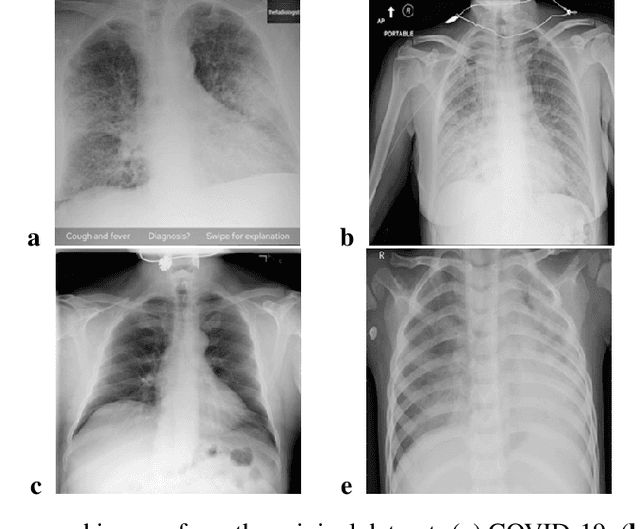

The availability of training data is one of the main limitations in deep learning applications for medical imaging. Data augmentation is a popular approach to overcome this problem. A new approach is a Machine Learning based augmentation, in particular usage of Generative Adversarial Networks (GAN). In this case, GANs generate images similar to the original dataset so that the overall training data amount is bigger, which leads to better performance of trained networks. A GAN model consists of two networks, a generator and a discriminator interconnected in a feedback loop which creates a competitive environment. This work is a continuation of the previous research where we trained StyleGAN2-ADA by Nvidia on the limited COVID-19 chest X-ray image dataset. In this paper, we study the dependence of the GAN-based augmentation performance on dataset size with a focus on small samples. Two datasets are considered, one with 1000 images per class (4000 images in total) and the second with 500 images per class (2000 images in total). We train StyleGAN2-ADA with both sets and then, after validating the quality of generated images, we use trained GANs as one of the augmentations approaches in multi-class classification problems. We compare the quality of the GAN-based augmentation approach to two different approaches (classical augmentation and no augmentation at all) by employing transfer learning-based classification of COVID-19 chest X-ray images. The results are quantified using different classification quality metrics and compared to the results from the literature. The GAN-based augmentation approach is found to be comparable with classical augmentation in the case of medium and large datasets but underperforms in the case of smaller datasets. The correlation between the size of the original dataset and the quality of classification is visible independently from the augmentation approach.